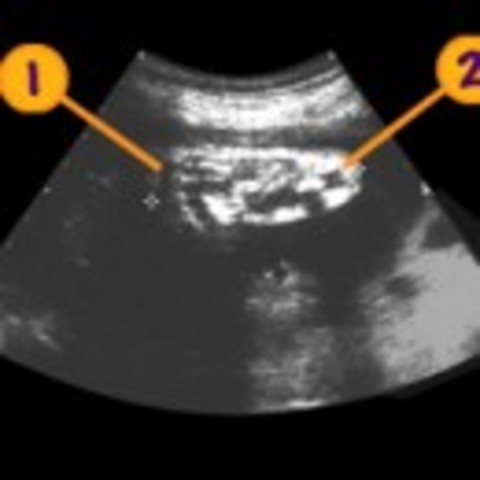

Hydrocephalus is due to a problem with the flow of the fluid that surrounds the brain. This fluid is called the cerebrospinal fluid, or CSF. It surrounds the brain and spinal cord, and helps cushion the brain. To treat hydrocephalus there needs to be a shunt implanted either in the brain or in the spinal cord.